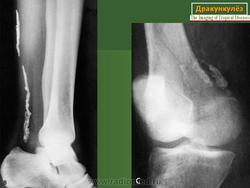

Дракункулез (ришта) - распространенный в тропиках и субтропиках гельминтоз, поражающий преимущественно местное население.

Человек заражается при употреблении некипяченой воды, в которой могут находиться личинки паразитов - циклопы. У человека самка ришты обитает в подкожной клетчатке, чаще всего нижних конечностей.

Спустя 8-14 месяцев после заражения на ноге (стопа) появляется пузырь (2-7 см) с головкой червя, тело которого может достигать 120 см в длину и прощупываться под кожей в виде тяжа. Болезнь сопровождается лихорадкой, тошнотой, рвотой, поносом, одышкой и крапивницей. Язва заживает примерно через месяц после удаления червя. У приезжих заболевание встречается редко.